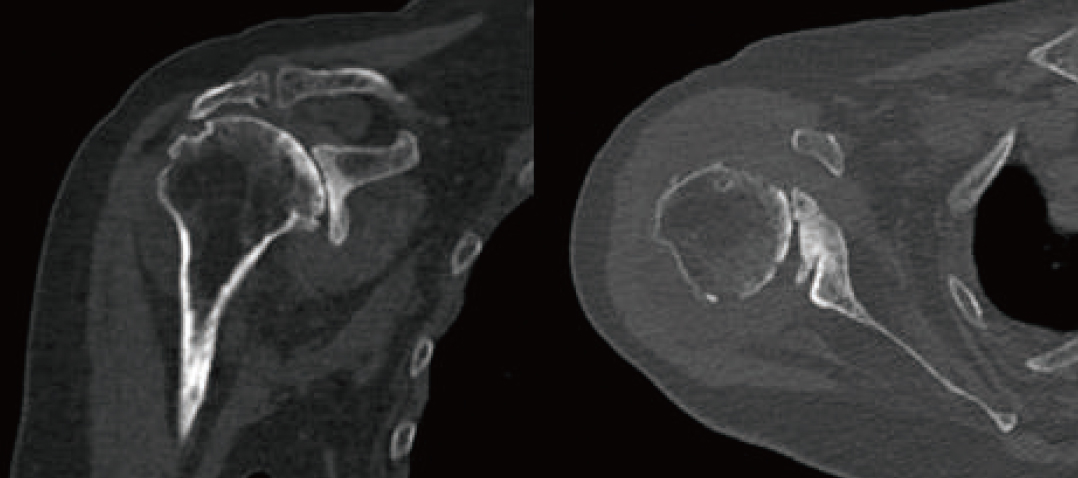

저자는 Glenoid의 glenoid vault가 14mm로 bone loss가 심한 Cuff tear arthropathy 환자에게 Navigation guided technique을 이용하여 Cortical bone augmentation을 시행하고 Glenoid baseplate를 성공적으로 고정하였고, 이 case를 공유하고자 한다. 81세 여환으로 Massive cuff teararthropathy(Hamada classification 5) 진단되었다. Glenoid의 bone loss가 심해서 인공관절의 glenoid baseplate를 삽입하기 힘든 구조였고(그림1) 이를 보완하기 위해 수술 시 Humeral head cutting시 생기는 cortical bone으로 glenoid에 augmentation을 시행하고 위에 baseplate를 대서 적절한 위치에 삽입하도록 계획을 세웠다. 예상대로 glenoid의 bone loss가 심하여 reaming이후에 baseplate를 삽입할 surface가 거의 남지 않았고 screw의 방향이 정확하게 가는 지 확인할 방법이 없었다. 하지만 Navigation(그림 2)의 guide에 따라 남아있는 glenoid의 bone stock에 최대한 긴 screw를 fixation 하였고 수술전에 planning 한대로(그림 3) humeral head의 cortical bone을 이용하여 augmentation을 시행한 뒤(그림 4)에 baseplate를 위치시켰고, 결과적으로 적절한 길이의 screw가 삽입될 수 있어 성공적으로 수술을 마쳤다. 수술 X-ray에서 인공관절이 수술 전 계획했던 대로 환자의 해부학적 위치에 맞게 제 위치에 적절히 삽입되었음을 확인할 수 있었다. 수술 후 cortical bone augmentation과 glenoid surface의 bone union이 촉진되도록 parathyroid hormone제제를 사용했다. 재활은 수술 후 환자는 bed side에서 pendulum 및 scapular stretching exercise를 자가 시행하였으며, 수술 1개월 후 보조 막대기를 이용하여 passive forward elevation 및 abduction을 했다. 수술 3개월 후 active shoulder ROM exercise를 시행했으며 수술 6개월 후 nearly full ROM을 회복하였다. 현재 환자는 수술 부위 통증도 거의 없으며 평소에 불편해하던 반대쪽 어깨도 수술 받고 싶어할 정도로 만족도가 높다.

그림 1, 수술 전 환자의 CT, Glenoid bone loss 및 deformity가 심해 RTSA glenoid component 삽입이 어려워 보인다.